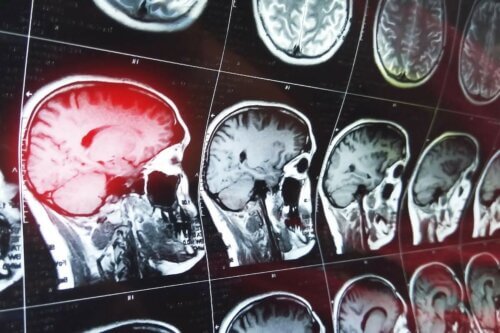

As causas das falhas de memória causadas por confabulações em pacientes são o produto de danos à área frontal do cérebro. Em particular, a área afetada é a anterior basal, onde se encontram as áreas orbitofrontal e ventromedial.